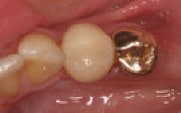

Figure 1

Initial situation:

Decay, fractured buccal cusp and unsupported lingual cusp on tooth

No. 20, buccal view.